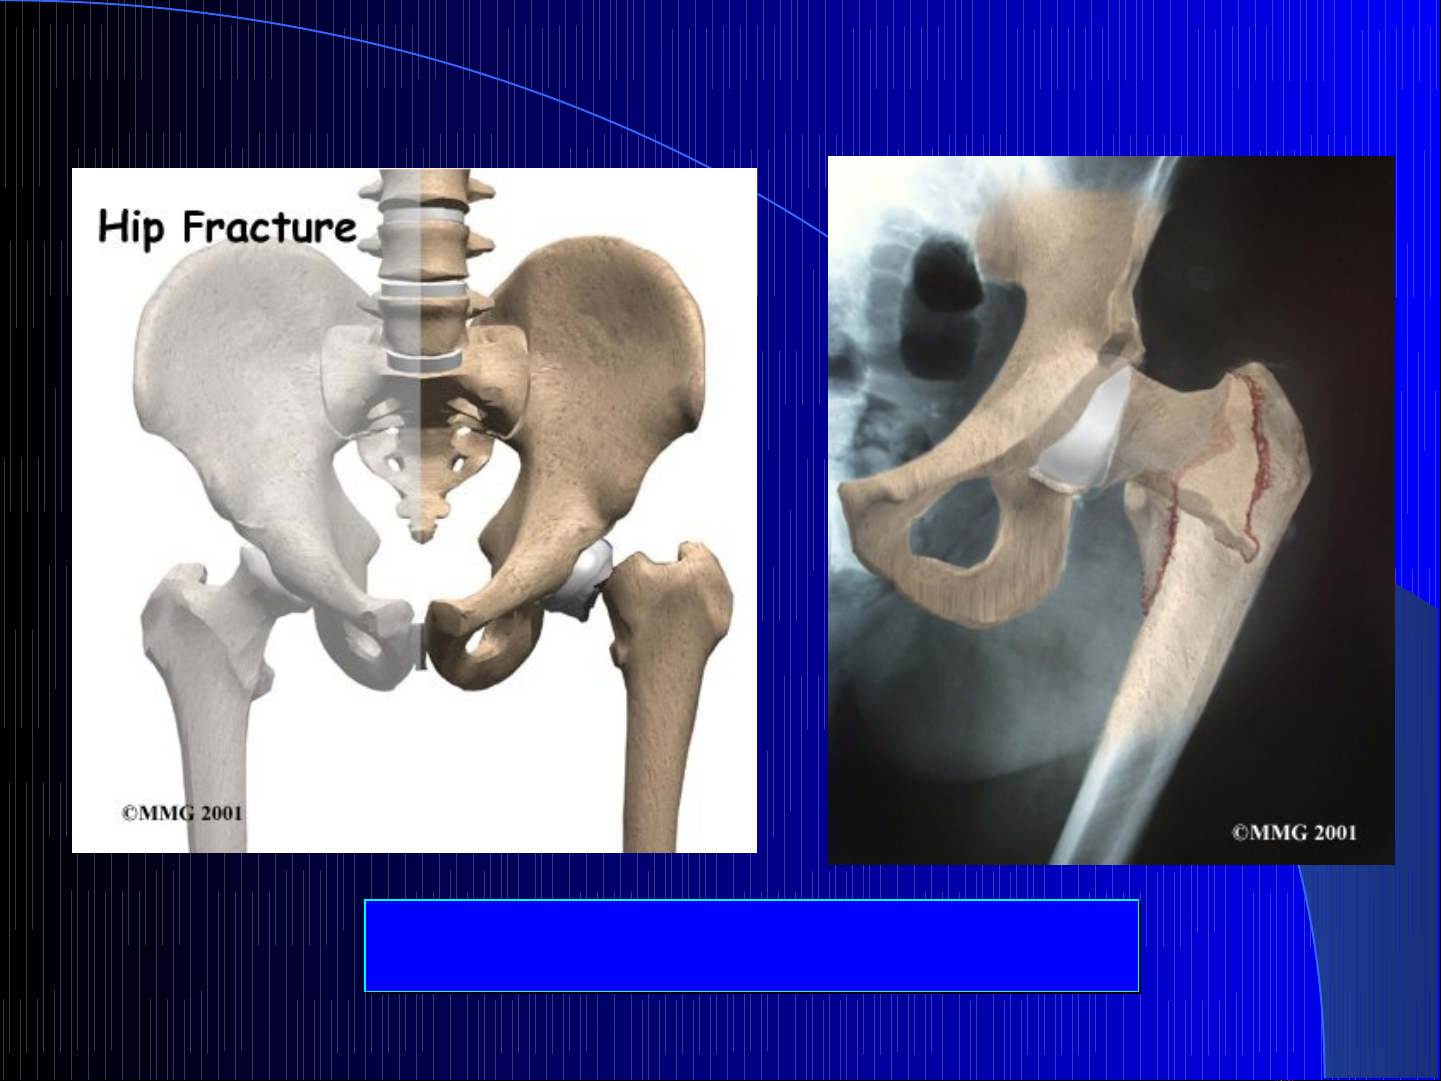

Các lo i gãy c x ng đùiạ ổ ươ